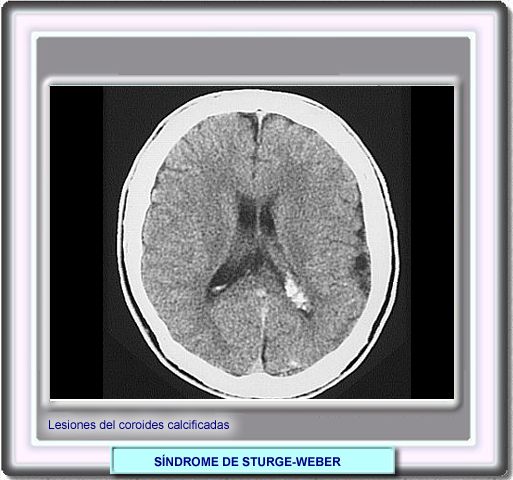

Algunos pacientes muestran una lesiones anchas y calcificadas en el plexo coroides en las imagenes en T2. La hiperintensidad observada puede ser debida a un edema o también a una ralentazación de la circulación venosa